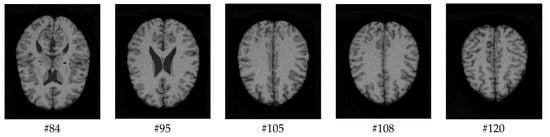

With regard to the T1-weighted MRI brain datasets, the performance of the HMRF-WOA was evaluated for 20 normal subjects. Figure 18 shows some slices of one subject (slices 20, 28, 32, 35, and 39); Figure 18a presents the initial slices images, (b) represents the ground truth segmentation, and (c) shows the HMRF-WOA segmentation results.

Moreover, Figure 18 illustrates the segmentation results of the proposed algorithm using MR brain images from the IBSR database. Figure 18a presents the slices of the original brain image; Figure 18b is the ground truth slice images; and Figure 18c shows the segmented brain MR images using the HMRF-WOA approach on the sample image of one subject. GM is shown in yellow, WM in red, CSF in green, and the background in blue.

Figure 18. Segmentation results of IBSR dataset: (a)—initial images; (b)—ground truth images; (c)—segmentation results.

Computers 13 00124 g018aComputers 13 00124 g018b